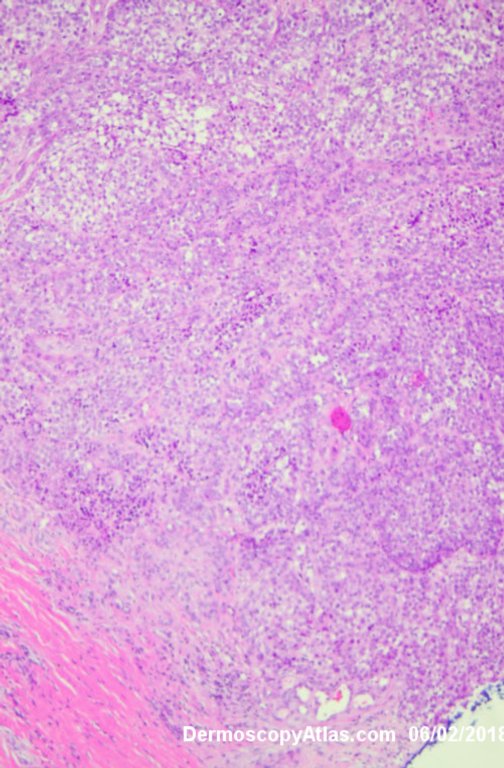

Image Number #3421 (Melanoma invasive)

Site: Leg

Diagnosis: Melanoma invasive

Description: Multiple colours in this pigmented lesion on the lower leg. New pink area

Lady in her early 80s who presented with this lesion on her ankle. The pigmented area had been there for some time but the pink area was bleeding and new. Shave of surrounding area and a punch biopsy of the new pink area showed mainly surrounding in situ melanoma with invasive melanoma in the pink area 1.8 mm thick. Having a 2cms margin excision of the whole area and a graft.